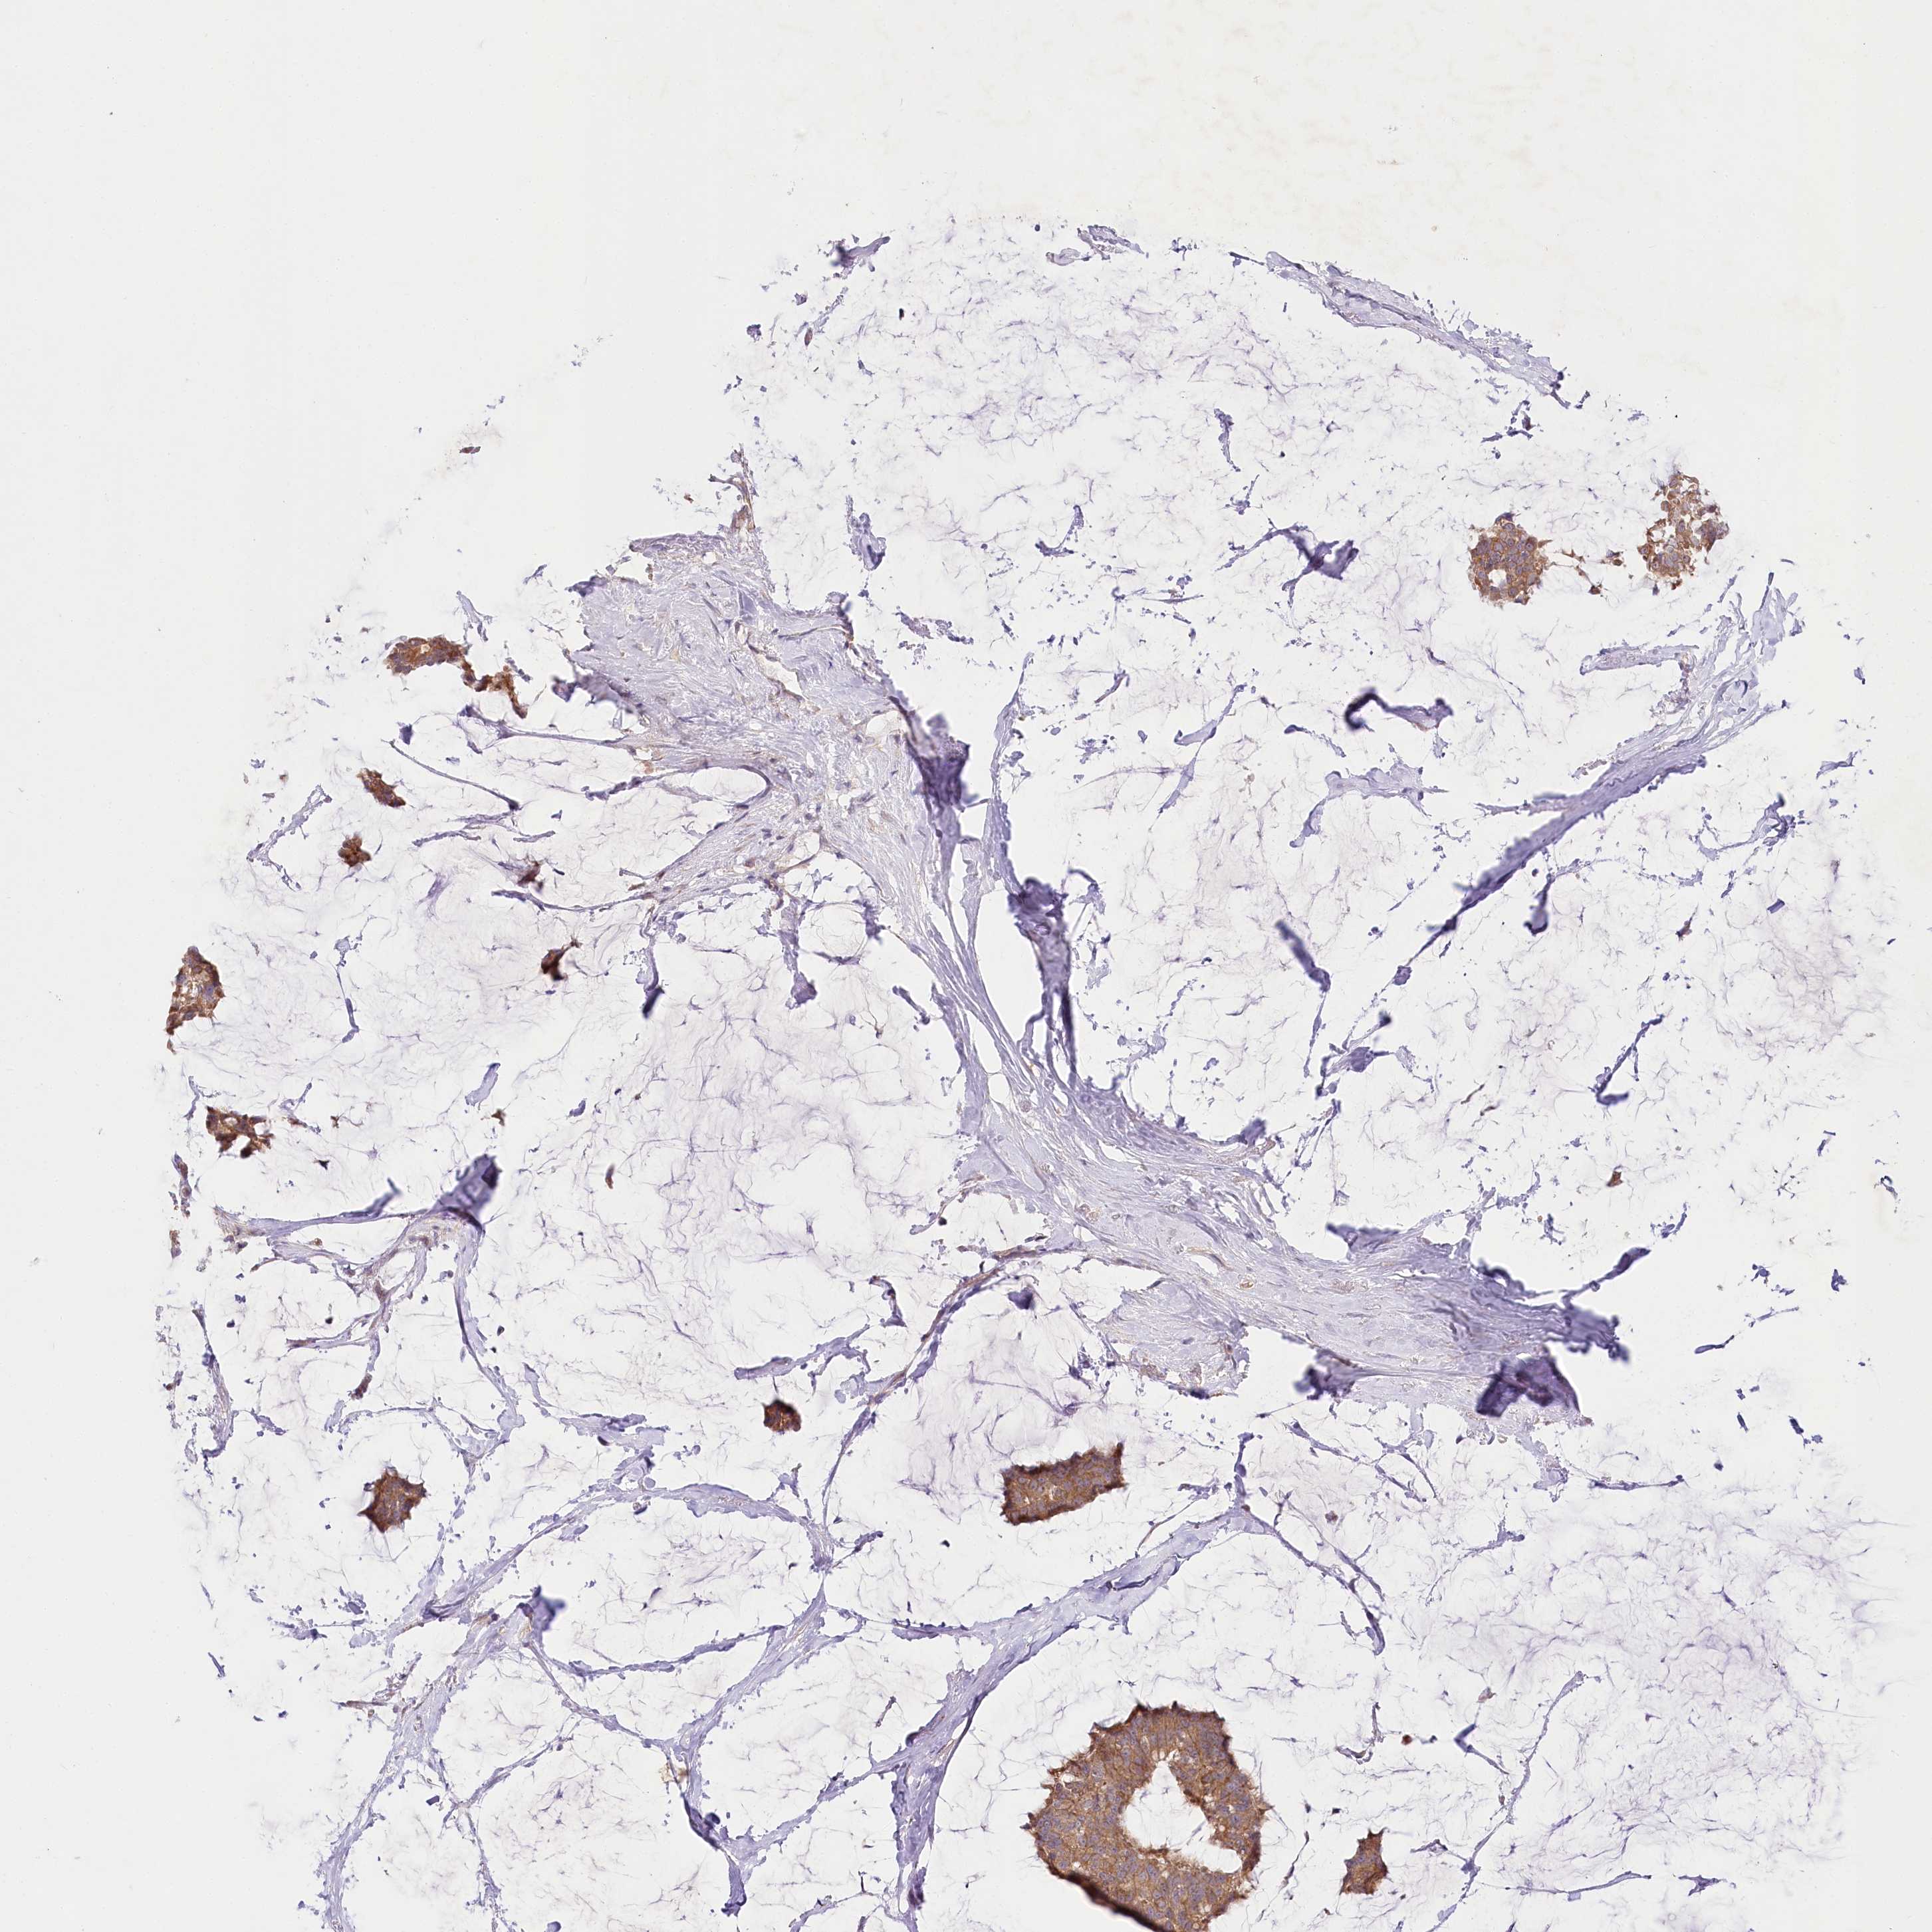

BRCA TCGA BRCA VALIDATION PROTEIN EXPRESSION

ANTIBODIES

AND

VALIDATION